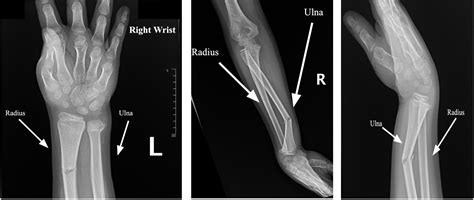

Comminuted, displaced, and angulated distal radial and ulnar metaphyseal fractures after a ...

TitleComminuted, displaced, and angulated distal radial and ulnar metaphyseal fractures after a ...